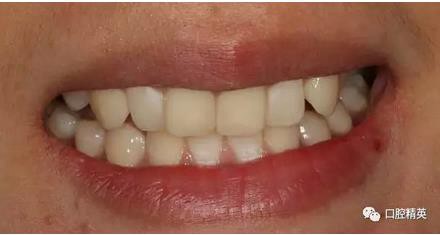

修復(fù)體戴入

口內(nèi)正側(cè)位及切端特寫

從側(cè)位照可看出遠(yuǎn)中切角略有回收

對(duì)比來看基本達(dá)到患者預(yù)期